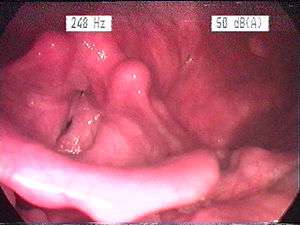

Endoscopic image of an inflamed larynx caused by acid reflux. | |

The larynx itself will often show erythema (reddening) and edema (swelling). This can be seen with laryngoscopy or stroboscopy (method depends on the type of laryngitis).[7]:108 Other features of the laryngeal tissues may include:

- Redness of the laryngeal tissues (acute)

- Dilated blood vessels (acute)

- Thick, yet dry laryngal tissue (chronic)

- Stiff vocal folds

- Sticky secretions between the vocal folds and nearby structures (the interarytenoid region)